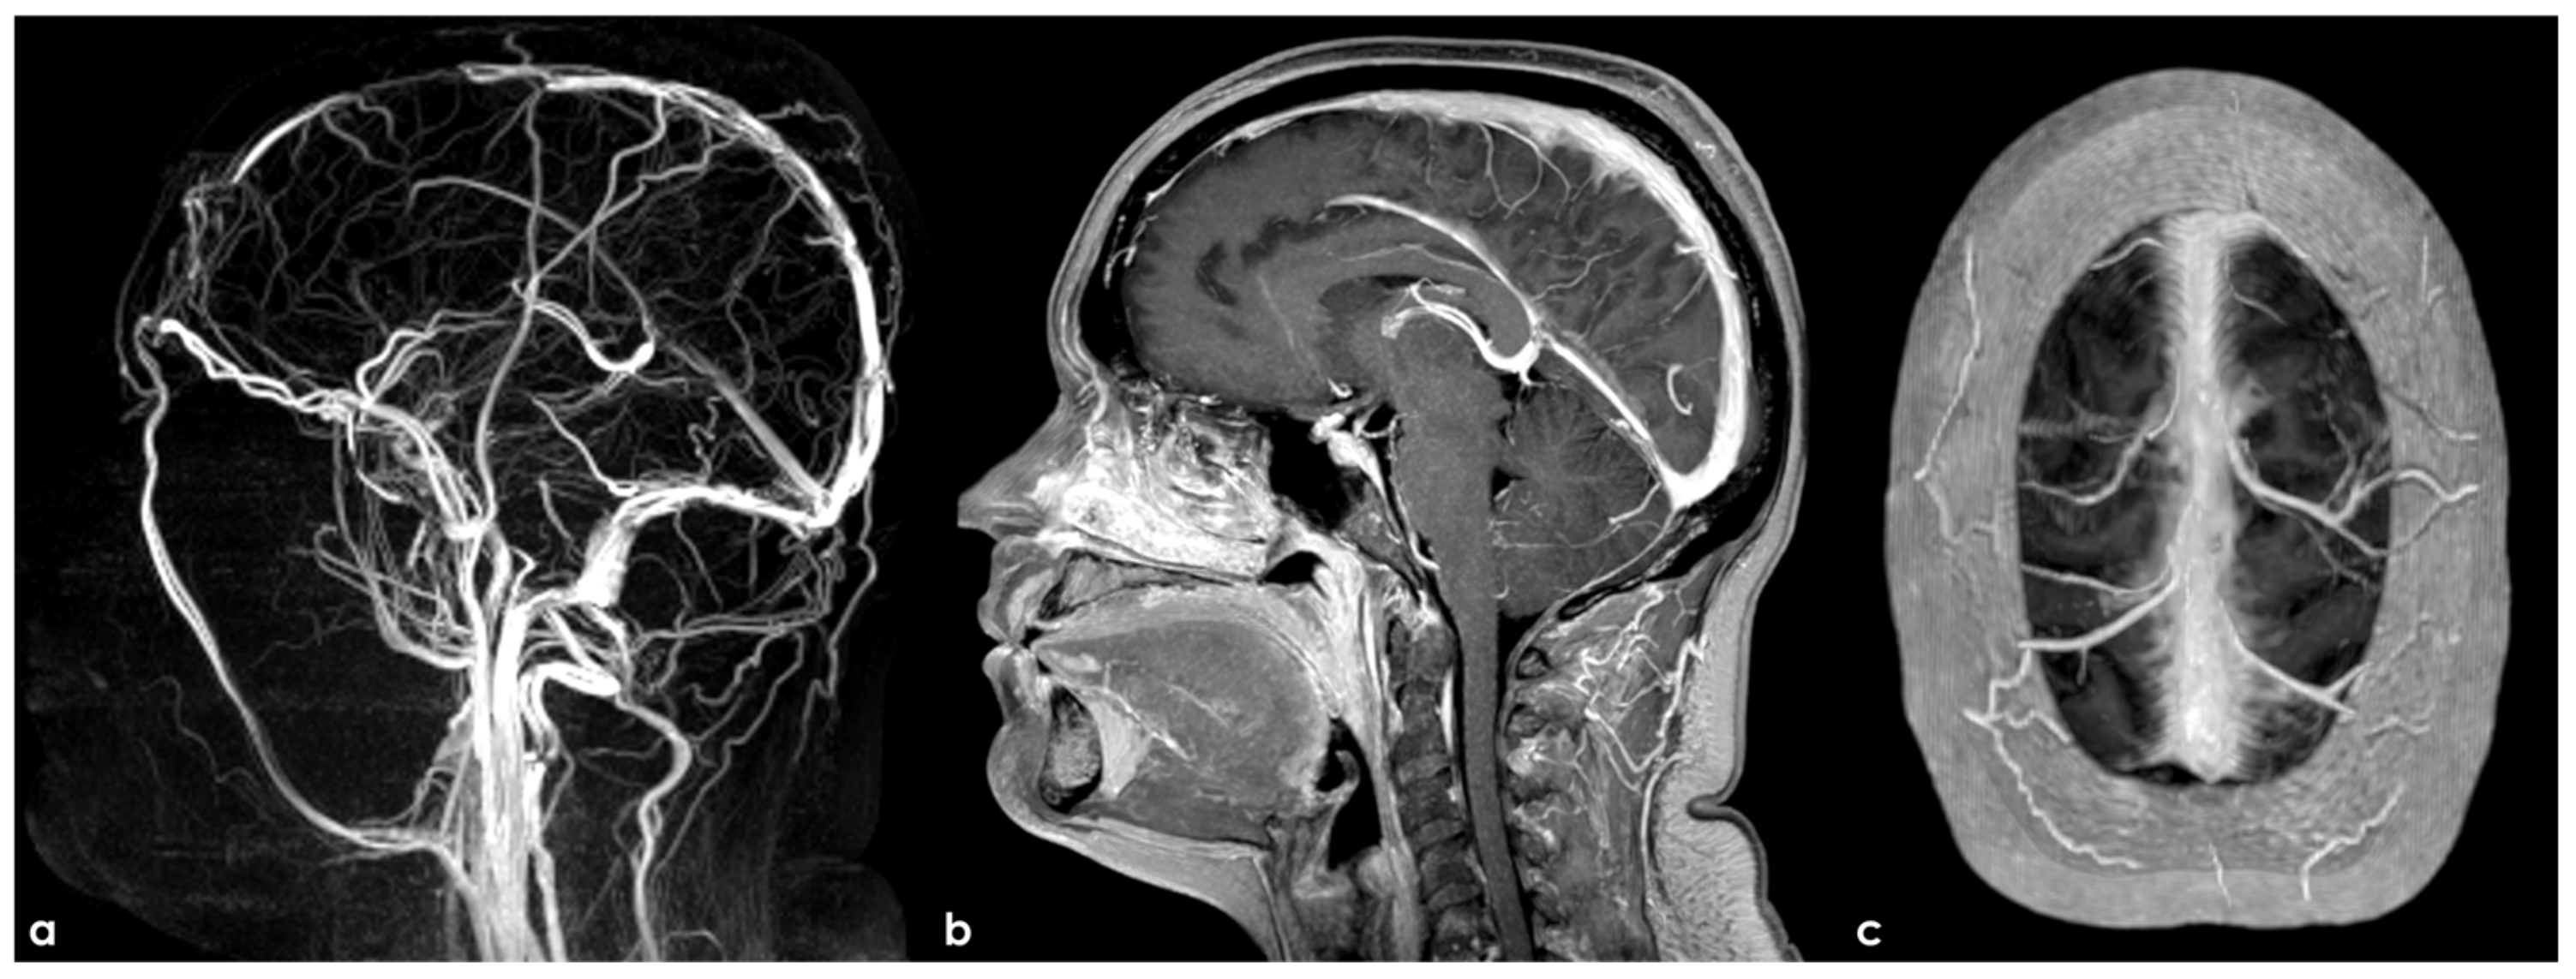

- Tian, Y.; Zhang, Z.; Jing, J.; Dong, K.; Mo, D.; Wang, Y. Anatomic variation of the lateral sinus in patients with idiopathic intracranial hypertension: Delineation with black-blood contrast-enhanced MRI. Front. Neurol. 2021, 12, 715857. [Google Scholar] [CrossRef]